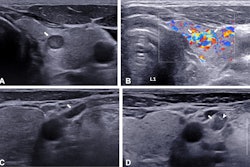

(A) Imaging shows conventional ultrasound in a 49-year-old female participant with a thyroid nodule (white arrows) detected on a previous ultrasound image two weeks prior. The nodule is solid, hypoechoic, and taller than wide with the punctate echogenic foci (yellow arrow) and lobulated margin in the right lobe. The maximum diameter is 10 mm. The American College of Radiology TI-RADS system is TR5 level. The proportion of cystic component is 0%. (B) The elastogram shows blue to indicate stiffness (arrows in transverse cross-section) in the nodule. (C) The CEUS image (nine seconds, the start of the wash-in period of the thyroid nodule) shows early-phase hypoenhancement intensity (arrows on transverse cross-section) with slow-infusion wash-in mode. (D) CEUS imaging (36 seconds, the end of the maximum enhancement and the start of the wash-out period in the thyroid parenchyma) shows heterogeneous enhancement uniformity (arrows on transverse cross-section). The whole CEUS shows low blood volume. Both the predicted value (0.9) according to the nomogram of the multimodaluty model and the management of TI-RADS recommended fine-needle aspiration to the thyroid nodule. The final pathologic diagnosis was papillary thyroid carcinoma, and the participant underwent microwave ablation to the thyroid nodule. Images and caption courtesy of RSNA.The team employed four multivariable models which incorporated patient age with nodule features on ultrasound, elastography features, and CEUS features. It also combined these into one multimodality model.